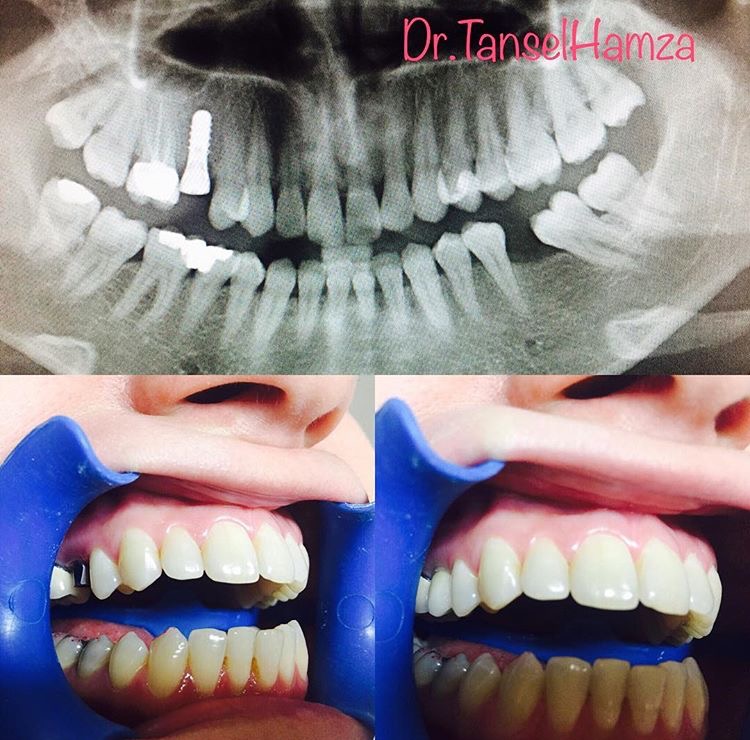

Tansel Hamza

Diş Estetiği ve İmplant (Bölüm 4)